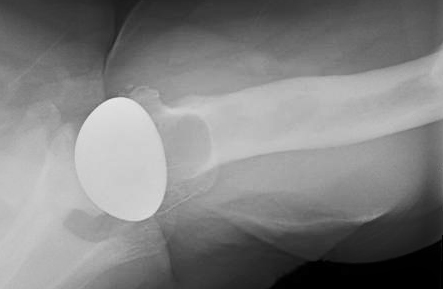

His x-rays show what appears to be an Arthrosurface implant in the proximal humerus. There is suggesting of lucency around the implant.

There was also a possible lytic lesion distal to the implant in the humeral canal. We obtained an MRI of the shoulder to evaluate for infection or an oncological process, but the MRI was unremarkable for either.